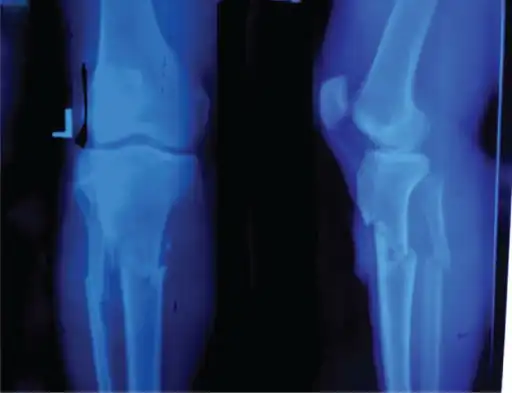

Tibial tuberosity avulsion

A tibial tuberosity avulsion fracture is an incomplete or complete separation of the tibial tuberosity from the tibia. This occurs as a result of a violent contraction of the quadriceps muscles, most often as a result of a high-power jump. Incomplete fractures are usually treatable with the traditional RICE (rest, ice, compression, elevation) method, but complete/displaced fractures will most often require surgery to pin the tuberosity back in place. Tibial tuberosity avulsions occur most often in teenagers that engage in a large amount of sporting activities, and many studies have shown a history with Osgood-Schlatter's disease to be linked to the fracture.